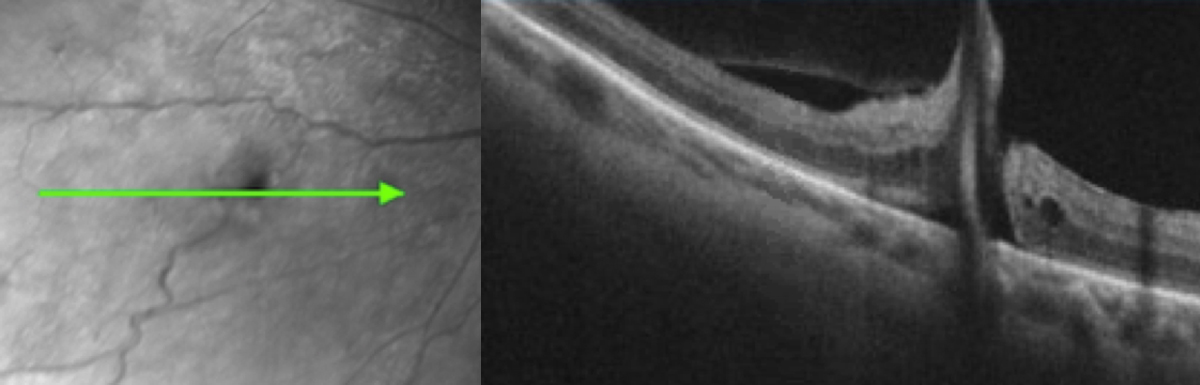

High-definition spectral-domain OCT (SD-OCT) revealed a partial posterior vitreous detachment (PVD) and traction on a vessel leading to the vitreous hemorrhage and a small retinal break (Figure 2). A shallow neurosensory detachment was also noted on imaging (Figure 3).

Figure 2: High-definition spectral-domain OCT OS showed an isolated full-thickness retinal defect with partial posterior vitreous detachment.